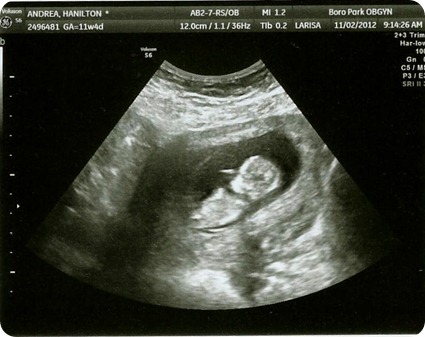

I shared a pregnancy update last week. I posted that I was 12 weeks. It was either “Mommy Brain” or excitement…I miscounted. I was really only 11 weeks. 12 weeks comes on Monday. But I had a pre-natal visit today so I have a couple of new pictures to show you!

The babies are measuring fine, and the heart rates are perfect. My due date is fluctuated slightly based on the babies’ sizes, but since it’s so early they are not actually going to change my due date. Monday will mark the end of my first trimester, so hopefully that means some more energy coming my way!

{click to enlarge}

Baby A: {hoping this one is a girl… “A” like Andrea?}

Baby B: {maybe this one is a boy… “B” like Ben?”}